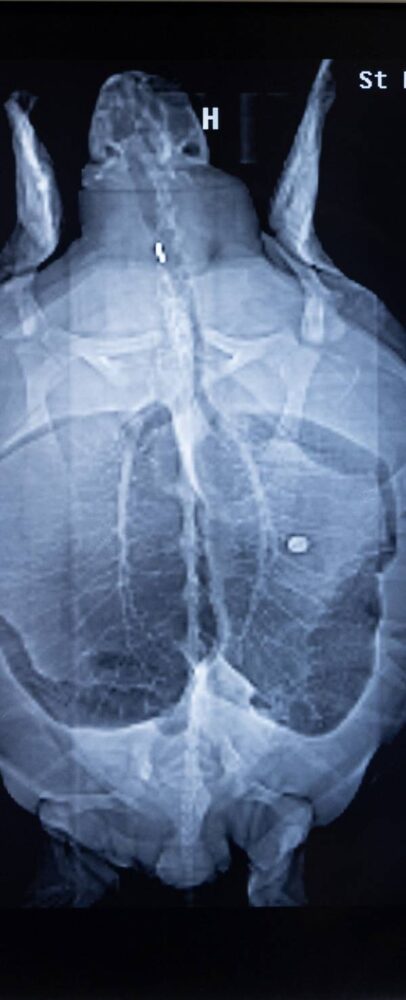

Pete had an X-ray taken and some blood drawn as part of an evaluation. That’s when the turtle was found to be female.

“There was a coin lodged in her esophagus,” Sattler said. “So I was thinking to myself that depending on what this coin is, that maybe it could help name her.”

The X-ray showed there were actually two coins — a dime and a nickel — both of which have since disappeared. They chose Nickel for her name.